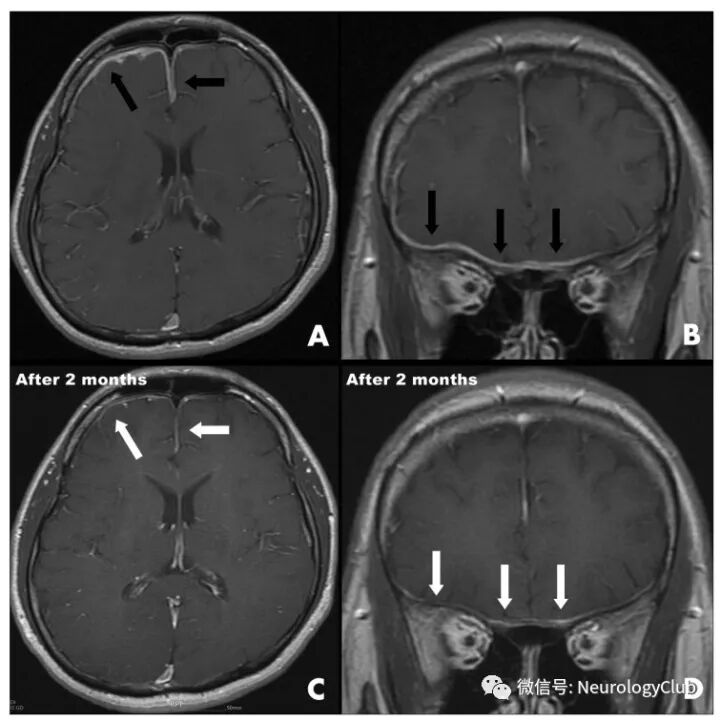

脑膜病变

(图21:NBD患者T1增强可见软脑膜强化)

(图22:A-B:增强T1可见弥漫硬脑膜强化;C-D:激素治疗后2月T1增强病灶较前改善)